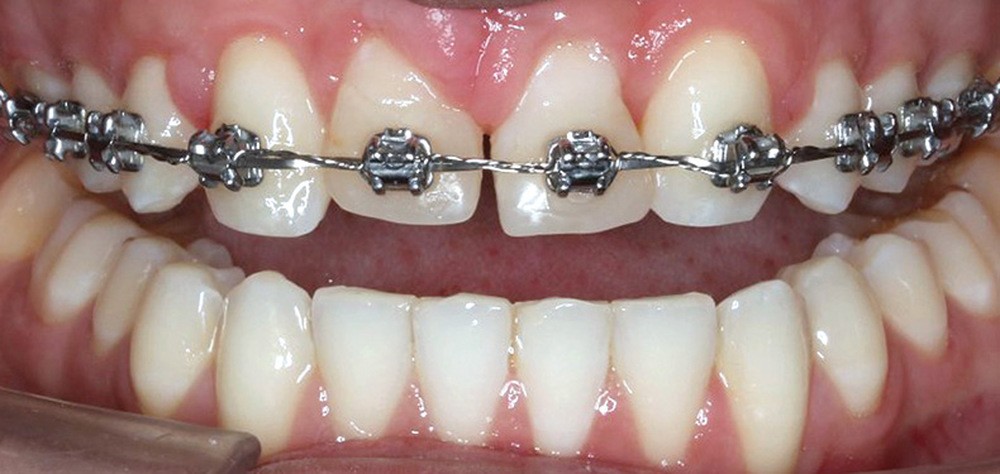

Traitement multi-attaches

Dans un premier temps, l’extraction des 11 et 21 est réalisée. Un bouton est collé sur la 13, visible dans l’alvéole de la 11 afin de permettre sa désinclusion (fig. 2). La traction se fait à l’aide d’un arc TMA .016 x .022 en overlay afin d’avoir un axe de traction horizontal et vestibulaire évitant une résorption de la 12 à cette étape (fig. 3a,b) [3]. Ne pouvant pas mettre d’arc de Nance du fait de la position palatine des incisives latérales, il est convenu que des minivis d’ancrage peuvent être nécessaires si une perte d’ancrage postérieure est constatée (ce qui n’est pas le cas).

Une fois la 13 à l’aplomb de son alvéole, une traction verticale de cette dent peut être réalisée. La 12 n’est pas prise en charge avant la correction de la transposition afin de limiter le risque de résorption de cette dent. La difficulté est alors la gestion des torques antérieurs perturbés, liés aux déplacements réalisés.